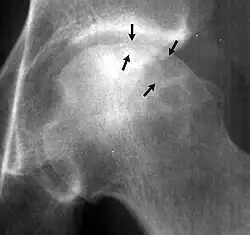

Crescent sign

A radiograph of a left hip joint, which reveals a thin, curvilinear lucent line parallel to the cortical margin of the femoral head, in a patient with avascular necrosis.

In radiology, the crescent sign is a finding on conventional radiographs that is associated with avascular necrosis.[1][2][3] It usually occurs later in the disease, in stage III of the four-stage Ficat classification system.[1] It appears as a curved subchondral radiolucent line that is often found on the proximal femoral or humeral head.[1] Usually, this sign indicates a high likelihood of collapse of the affected bone.[1] The crescent sign may be best seen in an abducted (frog-legged) position.[1][4]